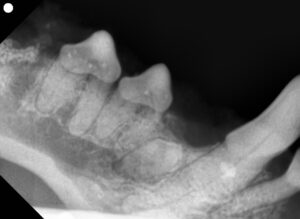

| ステージ 4 | 歯の構造の大部分が破壊されている。 4a:歯冠と歯根が同程度に破壊 4b:歯冠の破壊が優位 4c:歯根の破壊が優位 | 歯が欠けていたり、穴があいているように見えることも。症状が進行しやすく、感染や膿瘍のリスクも。基本的に抜歯が推奨。 |

| ステージ 5 | 歯冠は消失し、歯根が歯肉や骨と癒合(アンキローシス)している。 | 肉眼では歯がなくなって見える。レントゲン上で骨と癒着していることがわかる。処置の必要がない場合もあるが、場合によっては外科的に除去が必要。 |

吸収された歯は元に戻らないため、進行度に応じて抜歯処置が一般的です。

特にステージ3以降は痛みや感染リスクが高く、治療を急ぐ必要があります。